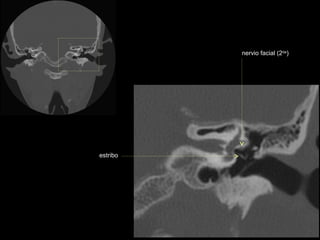

nervio facial (2da)

nervio facial (1era)

conducto auditivo interno

cresta falciforme

promontorio

estribo

ventana oval